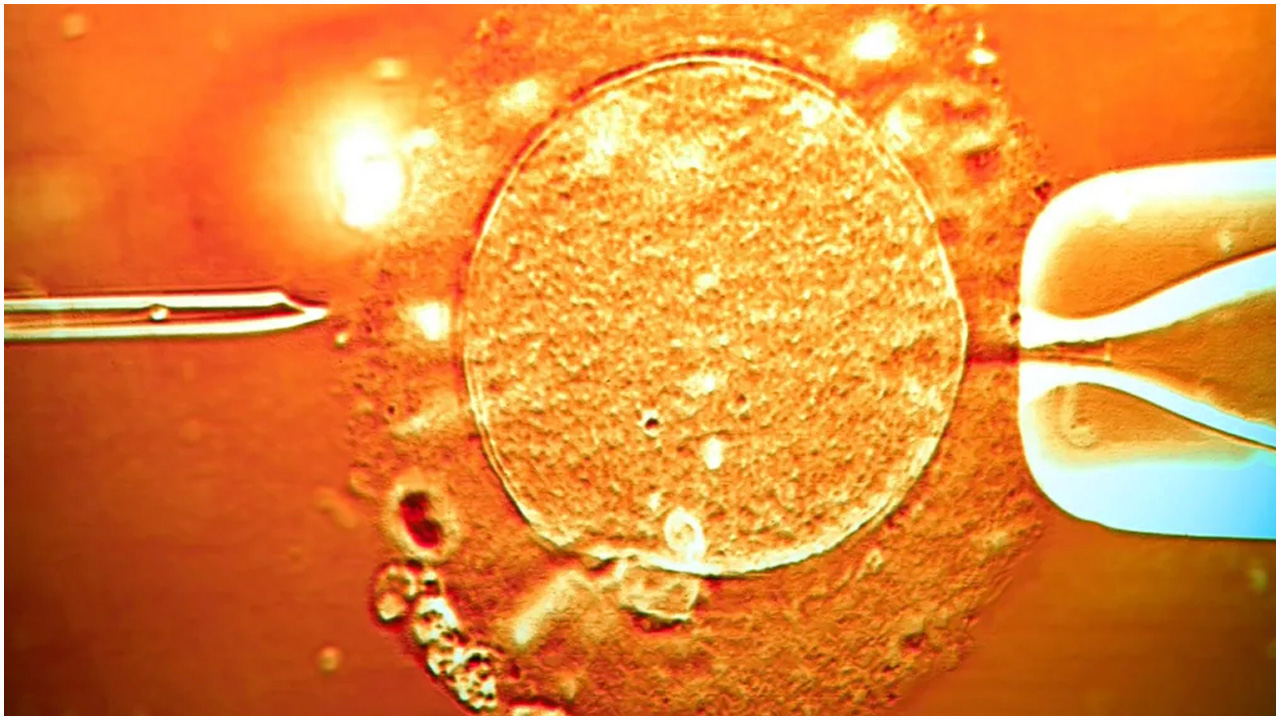

ক্যানসার সৃষ্টিকারী জিনবাহী দাতার শুক্রাণুতে ২০০ শিশুর জন্ম

শরীরে ক্যানসারের ঝুঁকি বৃদ্ধিকারী জিনের পরিবর্তন থাকলেও তা জানতেন না এক শুক্রাণুদাতা। জিনগত এই পরিবর্তনের বিষয়ে না জেনেই শুক্রানু দান করে অন্তত ১৯৭ শিশুর জন্ম দিয়েছেন তিনি। ইউরোপীয় ব্রডকাস্টিং ইউনিয়নের ইনভেস্টিগেটিভ জার্নালিজম নেটওয়ার্কের অনুসন্ধানে চাঞ্চল্যকর এই তথ্য উঠে এসেছে।

২০০৫ সালে ছাত্রাবস্থায় পারিশ্রমিক নিয়ে বেনামে শুক্রাণু দান শুরু করেন ওই ব্যক্তি। প্রায় ১৭ বছর ধরে নারীরা তার শুক্রাণু ব্যবহার করেছেন। তিনি সুস্থ ছিলেন এবং স্ক্রিনিং পরীক্ষায় উত্তীর্ণও হন। তবে জন্মের আগেই তার শরীরের কিছু কোষের ডিএনএ পরিবর্তিত হয়। এতে ক্ষতিগ্রস্ত হয় টিপি৫৩ নামের জিন; যা শরীরকে ক্যানসার থেকে রক্ষা করার ক্ষেত্রে গুরুত্বপূর্ণ ভূমিকা পালন করে।

দাতার শরীরের বেশিরভাগ কোষে ওই বদল পাওয়া যায়নি। তবে তার শুক্রাণুর প্রায় ২০ শতাংশে বিপজ্জনক পরিবর্তন লক্ষ্য করা যায়। আক্রান্ত শুক্রাণু থেকে জন্ম নেওয়া শিশুদের শরীরের প্রতিটি কোষেই এই ত্রুটি দেখা যায়।